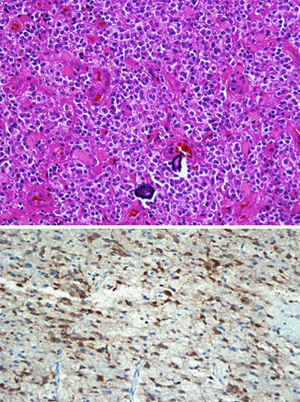

Wrensch and Jenkins found that having the “G,” or guanine, version of this SNP — rather than the more common “A” adenine version — was strongly associated with slower growing gliomas.

“Understanding how this variant causes people to get these less aggressive, but still lethal, tumors will be extremely important,” Wrensch said. “It may eventually lead to methods to reverse the course of these tumors or possibly to prevent their formation.”

As part of their work, the researchers compared the sequence of the gene variant throughout mammalian evolution and found that it has been conserved as far back as the platypus. Computer modeling indicated that the region may be a microRNA, a special kind of nucleic acid that controls the activity of genetic messages within cells. The modeling places the SNP within the functional part of the microRNA, suggesting that a change in genetic code from an “A” to a “G” could have significant consequences. The research team is investigating whether the microRNA actually exists, and what its functional implications might be.